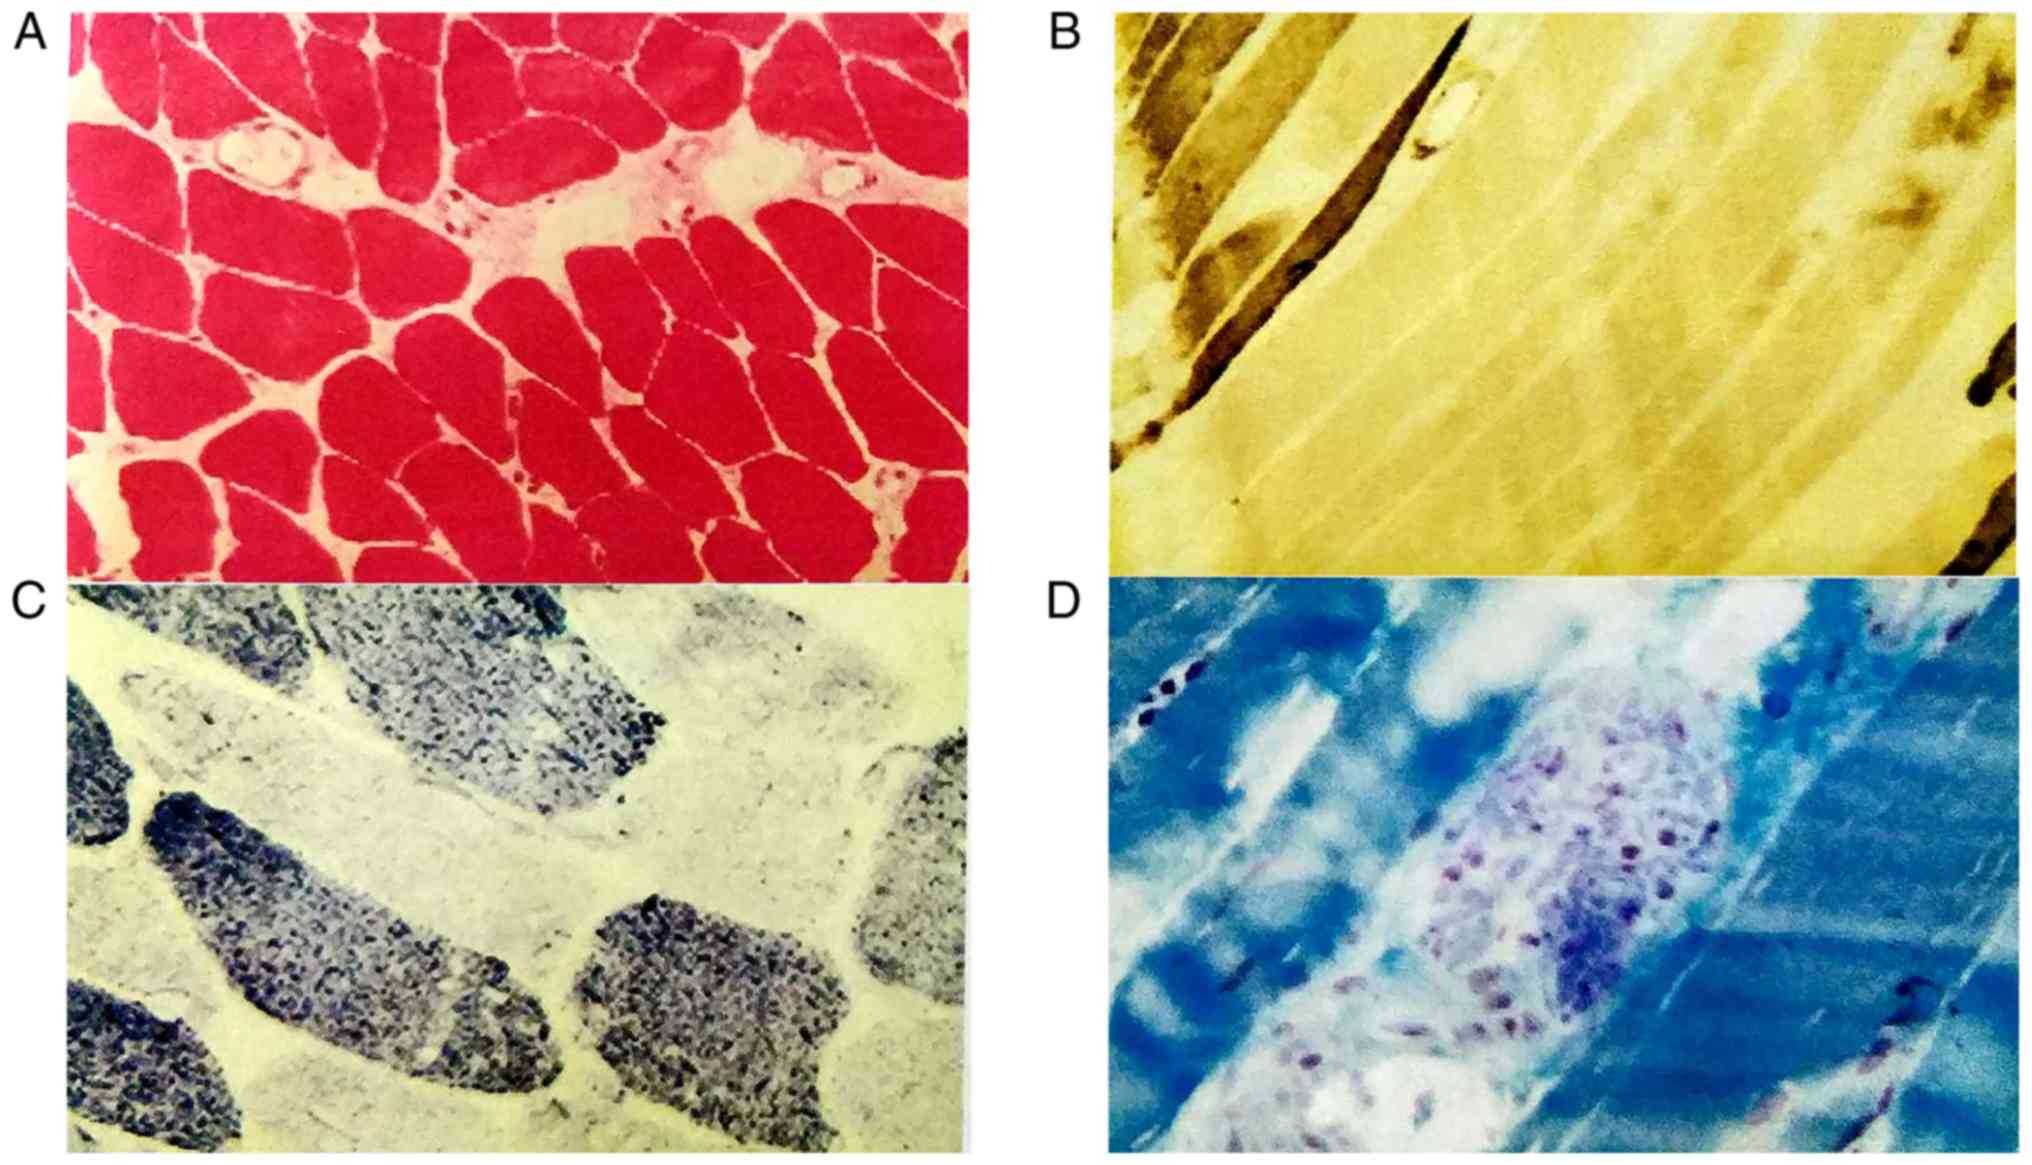

Biopsy specimens were taken from the patient's left

deltoid muscle. NADH enzyme staining indicated that small irregular

vacuoles were scattered in certain muscle fibers, and a small

amount of type I muscle fiber aggregated in edge particles

(Fig. 3C). ATPase staining revealed

clustering in some areas (Fig. 3B).

The pathological diagnosis was myogenic fiber disorder myopathy

(Fig. 3).

(Fig. 4D). Pathological diagnosis

was also myogenic fiber disorder myopathy, similar to that in

patient II.1 but with more obvious vacuoles in fibers.